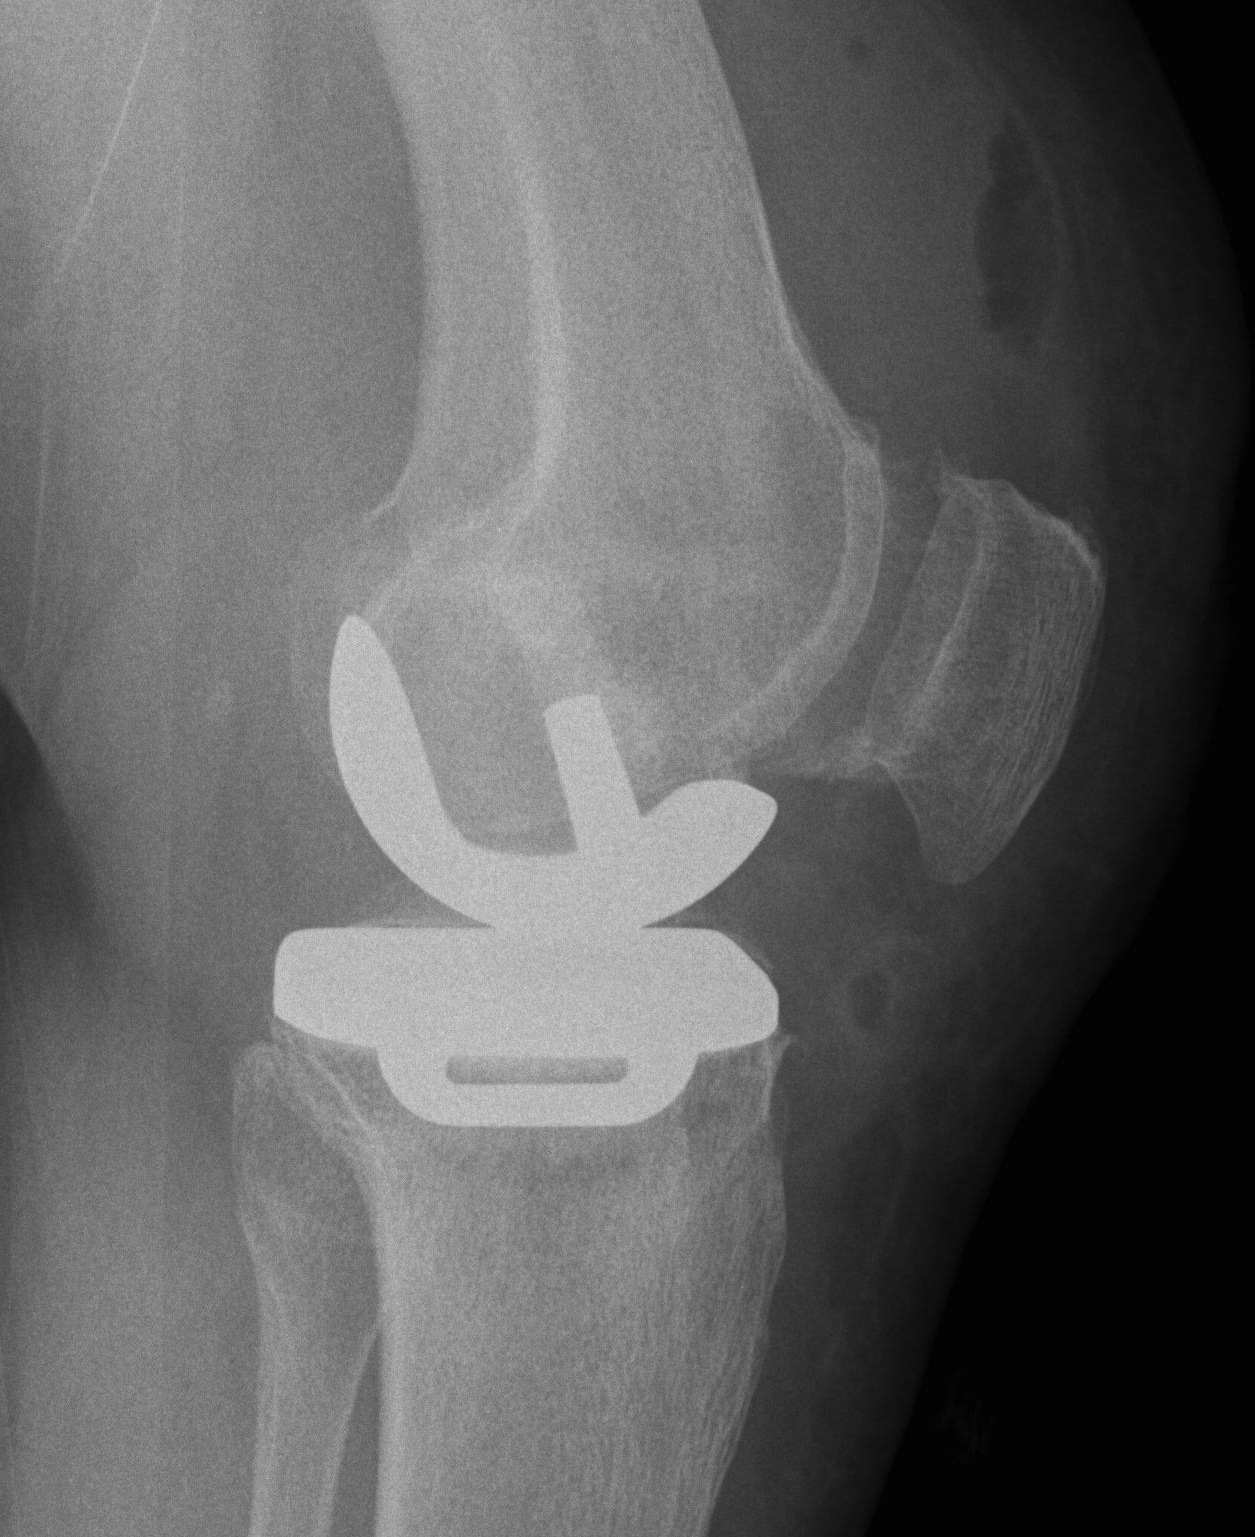

Patient 2